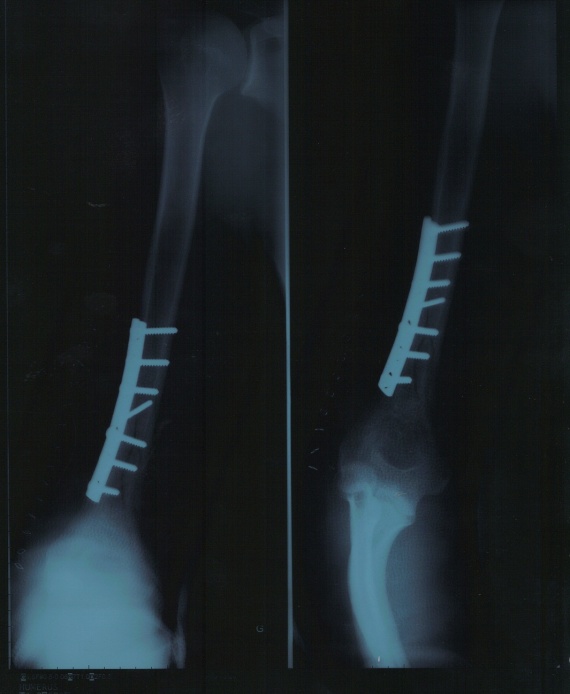

From forum.doctissimo.fr

Fracture spiroide humerus "bras de fer" Accidents sportifs FORUM Humerus Bras De Fer Learn about the causes, treatment, and recovery of a humeral shaft fracture, a break in the middle part of the humerus bone. En haut à l’épaule avec la scapula (anciennement omoplate), en bas au coude. L’humérus est un os long situé dans le bras. Humeral shaft fractures are common fractures of the diaphysis of the humerus, which may be associated. Humerus Bras De Fer.